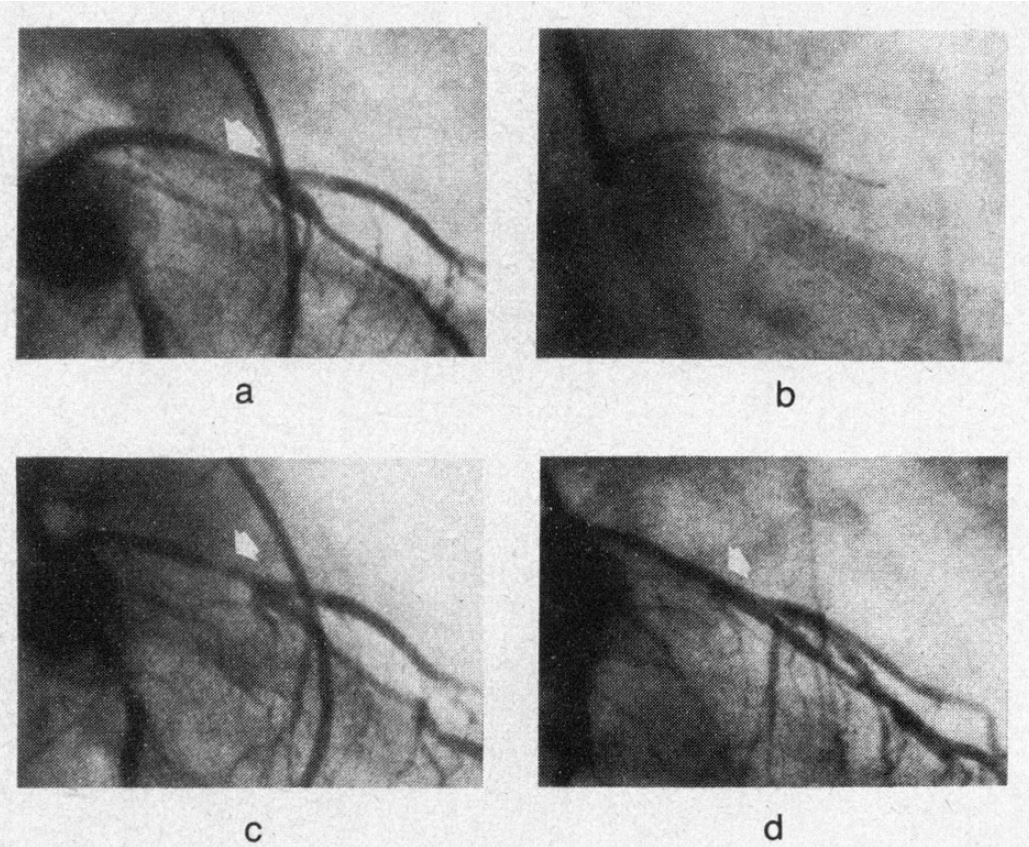

図6.バルーンカテーテルによる拡張術.38歳男性,狭心症.a. 術前,左前下行枝の狭窄,b. バルーンカテーテルによる拡張中,c. 術直後, d. 1ヵ月後.狭窄が消失している(→).

1974年,1976年の前報で,バルーンカテーテルによる下肢動脈の動脈硬化性閉塞症の治療に成功したGrüntzigが,冠動脈への応用を報告した論文で,現在も冠動脈狭窄の標準的治療法として広く行なわれているPTCAの初報で,PTCAという名称も初出である.1976年に,イヌの冠動脈で成功を報告後[4],1978年に5例の臨床例を短報として報告しており[5],本稿はこれを含む50例について,手技と成績を報告している.なお共著者のÅke Senningは心臓ペースメーカーの発明者である.

基本的な技術は,下肢動脈の場合と同じで,外径8~9Fの親カテーテルを冠動脈入口部に置き,これをガイドとしてダブルルーメンのバルーンカテーテルを冠動脈に挿入する.ただし下肢動脈の場合と異なり,ワイヤはバルーンカテーテルに固定されている.カテーテルの外径はなぜか記載がないが,バルーン拡張時の径は3~3.8mmとしている.拡張は4~5気圧,3~4秒,全体を通じて動脈の閉塞時間は15~20秒である.動物実験の報告では,バルーン拡張中の末梢虚血を懸念してローラーポンプで大腿動脈の血液を末梢に灌流しているが,臨床例では特にこのような処置は行なっていない.

狭心症患者50例 (パイパス術後8例を含む)に拡張術を施行し,32例で成功(狭窄率84%→34%)した.フォローアップ期間は最大18ヵ月と短いが,再拡張術,バイパス手術など追加治療が必要となった例は5例で,拡張は全体によく維持された.不成功の理由は,血管の屈曲など解剖学的理由のほか,多枝病変,バイパス術後例などに多かった.

この時点で,この方法の最も良い適応は,狭心症発症からの期間が短く,アテローマが柔らかい例で,バイパス術適応例の10~15%にとどまると,かなり控えめな結論になっているが,これがかえって幸いしてその後の好実績を生み,その後の普及につながったとも言われる.

なお本稿にも掲載されている第1例は,Adolph Backmanという狭心症の38歳男性で,バルーン拡張後,狭窄,自覚症状ともに消失したが(図6),2000年に安静時胸痛が再発し再検査を行い,23年前の治療部位を含め狭窄がないことが確認された[6].